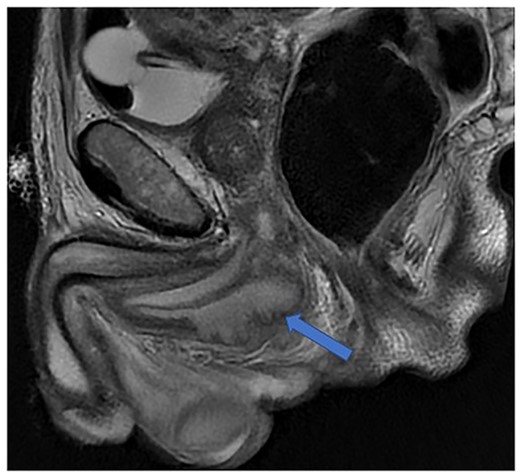

He was put on an empirical course of ciprofloxacin to treat a presumed complicated UTI, and a pelvic MRI was requested. Urine culture grew an Enterobacter cloacae organism. The MRI scan revealed a 7 × 3 cm perineal collection inferior to the prostate and adjacent to the membranous urethra, with increased wall enhancement and fluid with restricted diffusion, with a diagnosis of Cowper’s syringocele (Fig. 3).

Case 2: T2-weighted sagittal MRI image demonstrating a complex, cystic perineal collection (blue arrow), seen in relation to one of the corpus cavernosa (yellow arrow).